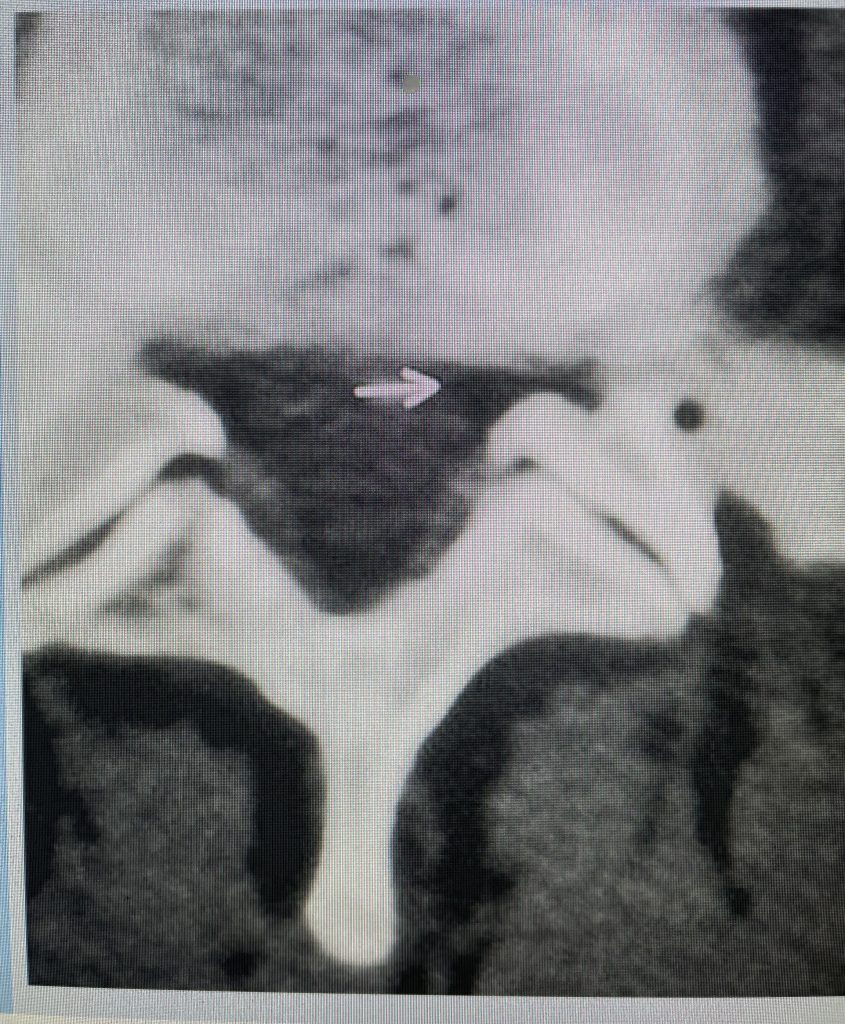

This 71 year-old male presents with a long history of progressive pain in the low back with radiation to both legs in the anterior thigh distribution, the left being worse than the right. He feels that his legs get weak. Standing and walking worsen the low back pain and lower extremity symptoms while sitting relieves the symptoms. He failed PT and epidural injections. Imaging studies revealed severe lateral recess stenosis do mainly to severed thickened ligament. He had severe lateral recess stenosis from L2-5 (Fig 4) as well as central stenosis. He also had a slight retrolisthesis at L3-4 and L4-5. He had on the left in particular a very enlarged protruded segment of thickened ligamentum in the subarticular recess at L3-4 (Fig 5) which was likely responsible for his left leg pain as the patient had symptoms of an L4-type syndrome. It was decided to perform a decompressive laminectomy from L2-5. Because of retrolisthesis it was decided to perform a noninstrumented onlay bone fusion or an in situ fusion from L3-5. In this case it was very important to decompress not only the thecal sac, but also the lateral recess with the thickened ligament at the point where the nerve makes its course into the forman. As a surgeon you must really undercut the facet joints to clear the lateral recess and feel how the nerve root with one’s instrument is being released as it enters the foramen. Postoperatively the patient had resolution of his leg pain, particularly on the left. In this case the most significant pathology was in the left L3-4 lateral recess, his symptoms and MRI findings correlated well which leads to the most successful operations.

Figure 4: Sagittal T2-weighted MRI demonstrating severe lateral recess stenosis from L2-L5 as well as slight retrolisthesis at L3-4 and L4-5.

Figure 5: Axial T2-weighted MRI demonstrating severe bilateral lateral recess stenosis secondary to thickened ligamentum flavum. Notice the prominence of the left ligamentum in the subarticular recess.